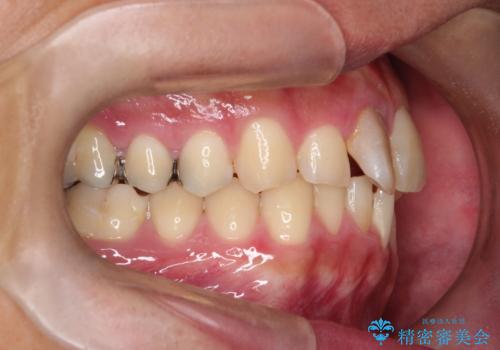

- 「上の前歯の捻じれと下の前歯のでこぼこを治したい」を主訴に来院された患者様です。

矯正検査の結果、非抜歯で矯正可能だったためインビザラインで治療を行いました。

アーチの拡大とIPRで叢生を改善いました。

11ヵ月で矯正を終える事ができ患者様も大変ご満足されていました。